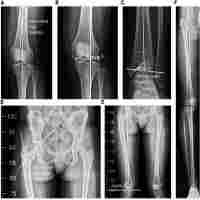

| Description | Perthes' disease is a self-limiting form of osteochondrosis of the capital femoral epiphysis of unknown aetiology that develops in children commonly between the ages of five and 12 years. Children under five and adolescents are affected much less frequently. The blood supply to part or all of the epiphysis becomes interrupted, leading to necrosis of the involved part. A varus derotation osteotomy is one of the most widely used methods of achieving containment. It entails an intertrochanteric or subtrochanteric osteotomy wherein the distal fragment is adducted and externally rotated to the same degree of abduction and internal rotation of the hip required to achieve containment. If passive internal rotation of the hip remains restricted after a period of traction or after the broomstick cast is removed a varus extension osteotomy is performed. A Chiari osteotomy is another way of improving coverage of the femoral head. Book Name: Paediatric Orthopaedics |